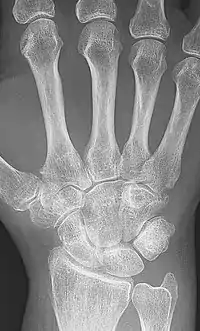

| A hand severely affected by rheumatoid arthritis. This degree of swelling and deformation does not typically occur with current treatment. | |